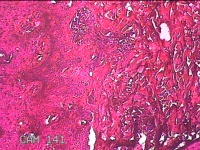

头部肿物

性别

男

年龄

18岁

临床诊断

头部局部肿物

一般病史

发现头顶部外凸结节半年余,近日出现局部破溃。

标本名称

大体所见

灰白暗红色肿物1.5x0.8x0.3cm一个,表面糜烂,结节表面有少许毛发,切开结节呈实性,切面灰白粉红色,质软。